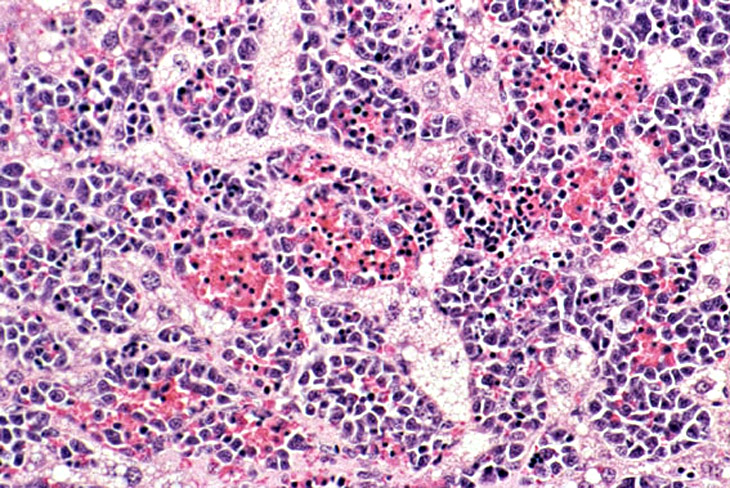

Erythroleukemia is a spontaneous hematopoietic neoplasm of Tg.AC mice characterized by marked hepatomegaly. The affected liver is infiltrated by metarubricytes and less differentiated erythroid precursors.

A higher magnification of hepatic erythroleukemia.